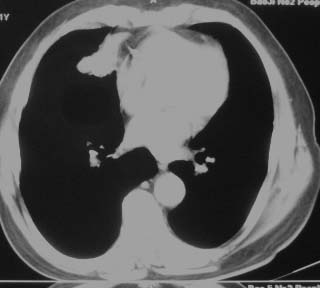

两肺多发异常密度,其中双上肺病变主要为纤维增殖性改变;右中肺内侧段病变密度相对均匀,无恶性特征,周围可见卫星灶和浸润表现,邻近胸膜稍增厚,所见纵隔层面无肿大淋巴结和胸腔积液。提示结核性改变。如果可能建议强化。

右肺中叶病灶境界基本清晰,肺窗上似见血管伸入,增强后明显强化,考虑动静脉瘘可能吧!

右肺中叶团片影,似多病灶融合而成,密度不均匀,边界清楚,周围见明显的索条及小结节,左肺亦见斑片影,纵隔窗未见肿大淋巴结.多考虑:肺内慢性炎性病变伴纤维化.

两肺多发异常密度,其中双上肺病变主要为纤维增殖性改变;右中肺内侧段病变密度相对均匀,无恶性特征,周围可见卫星灶和浸润表现,邻近胸膜稍增厚,所见纵隔层面无肿大淋巴结和胸腔积液。提示结核性改变.

右肺中叶软组织块(挑剔一下纵隔窗窗宽不理想),其周围可见多个类圆形结节,右肺上叶尖段见斑片、索条状致影,左肺小结节。